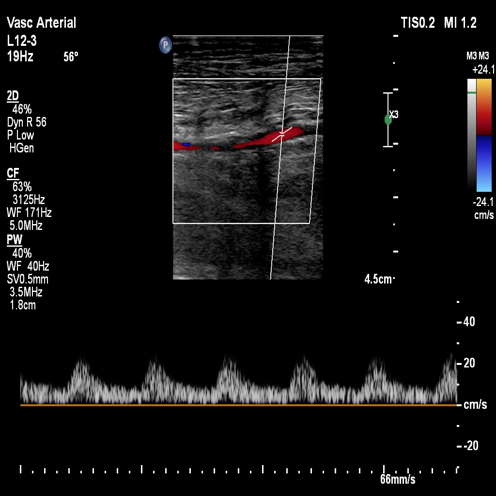

术前超声评估:提示腘动脉血栓。

图:胫腓干血栓及直径

胫后及腓动脉起始处彩色血流图